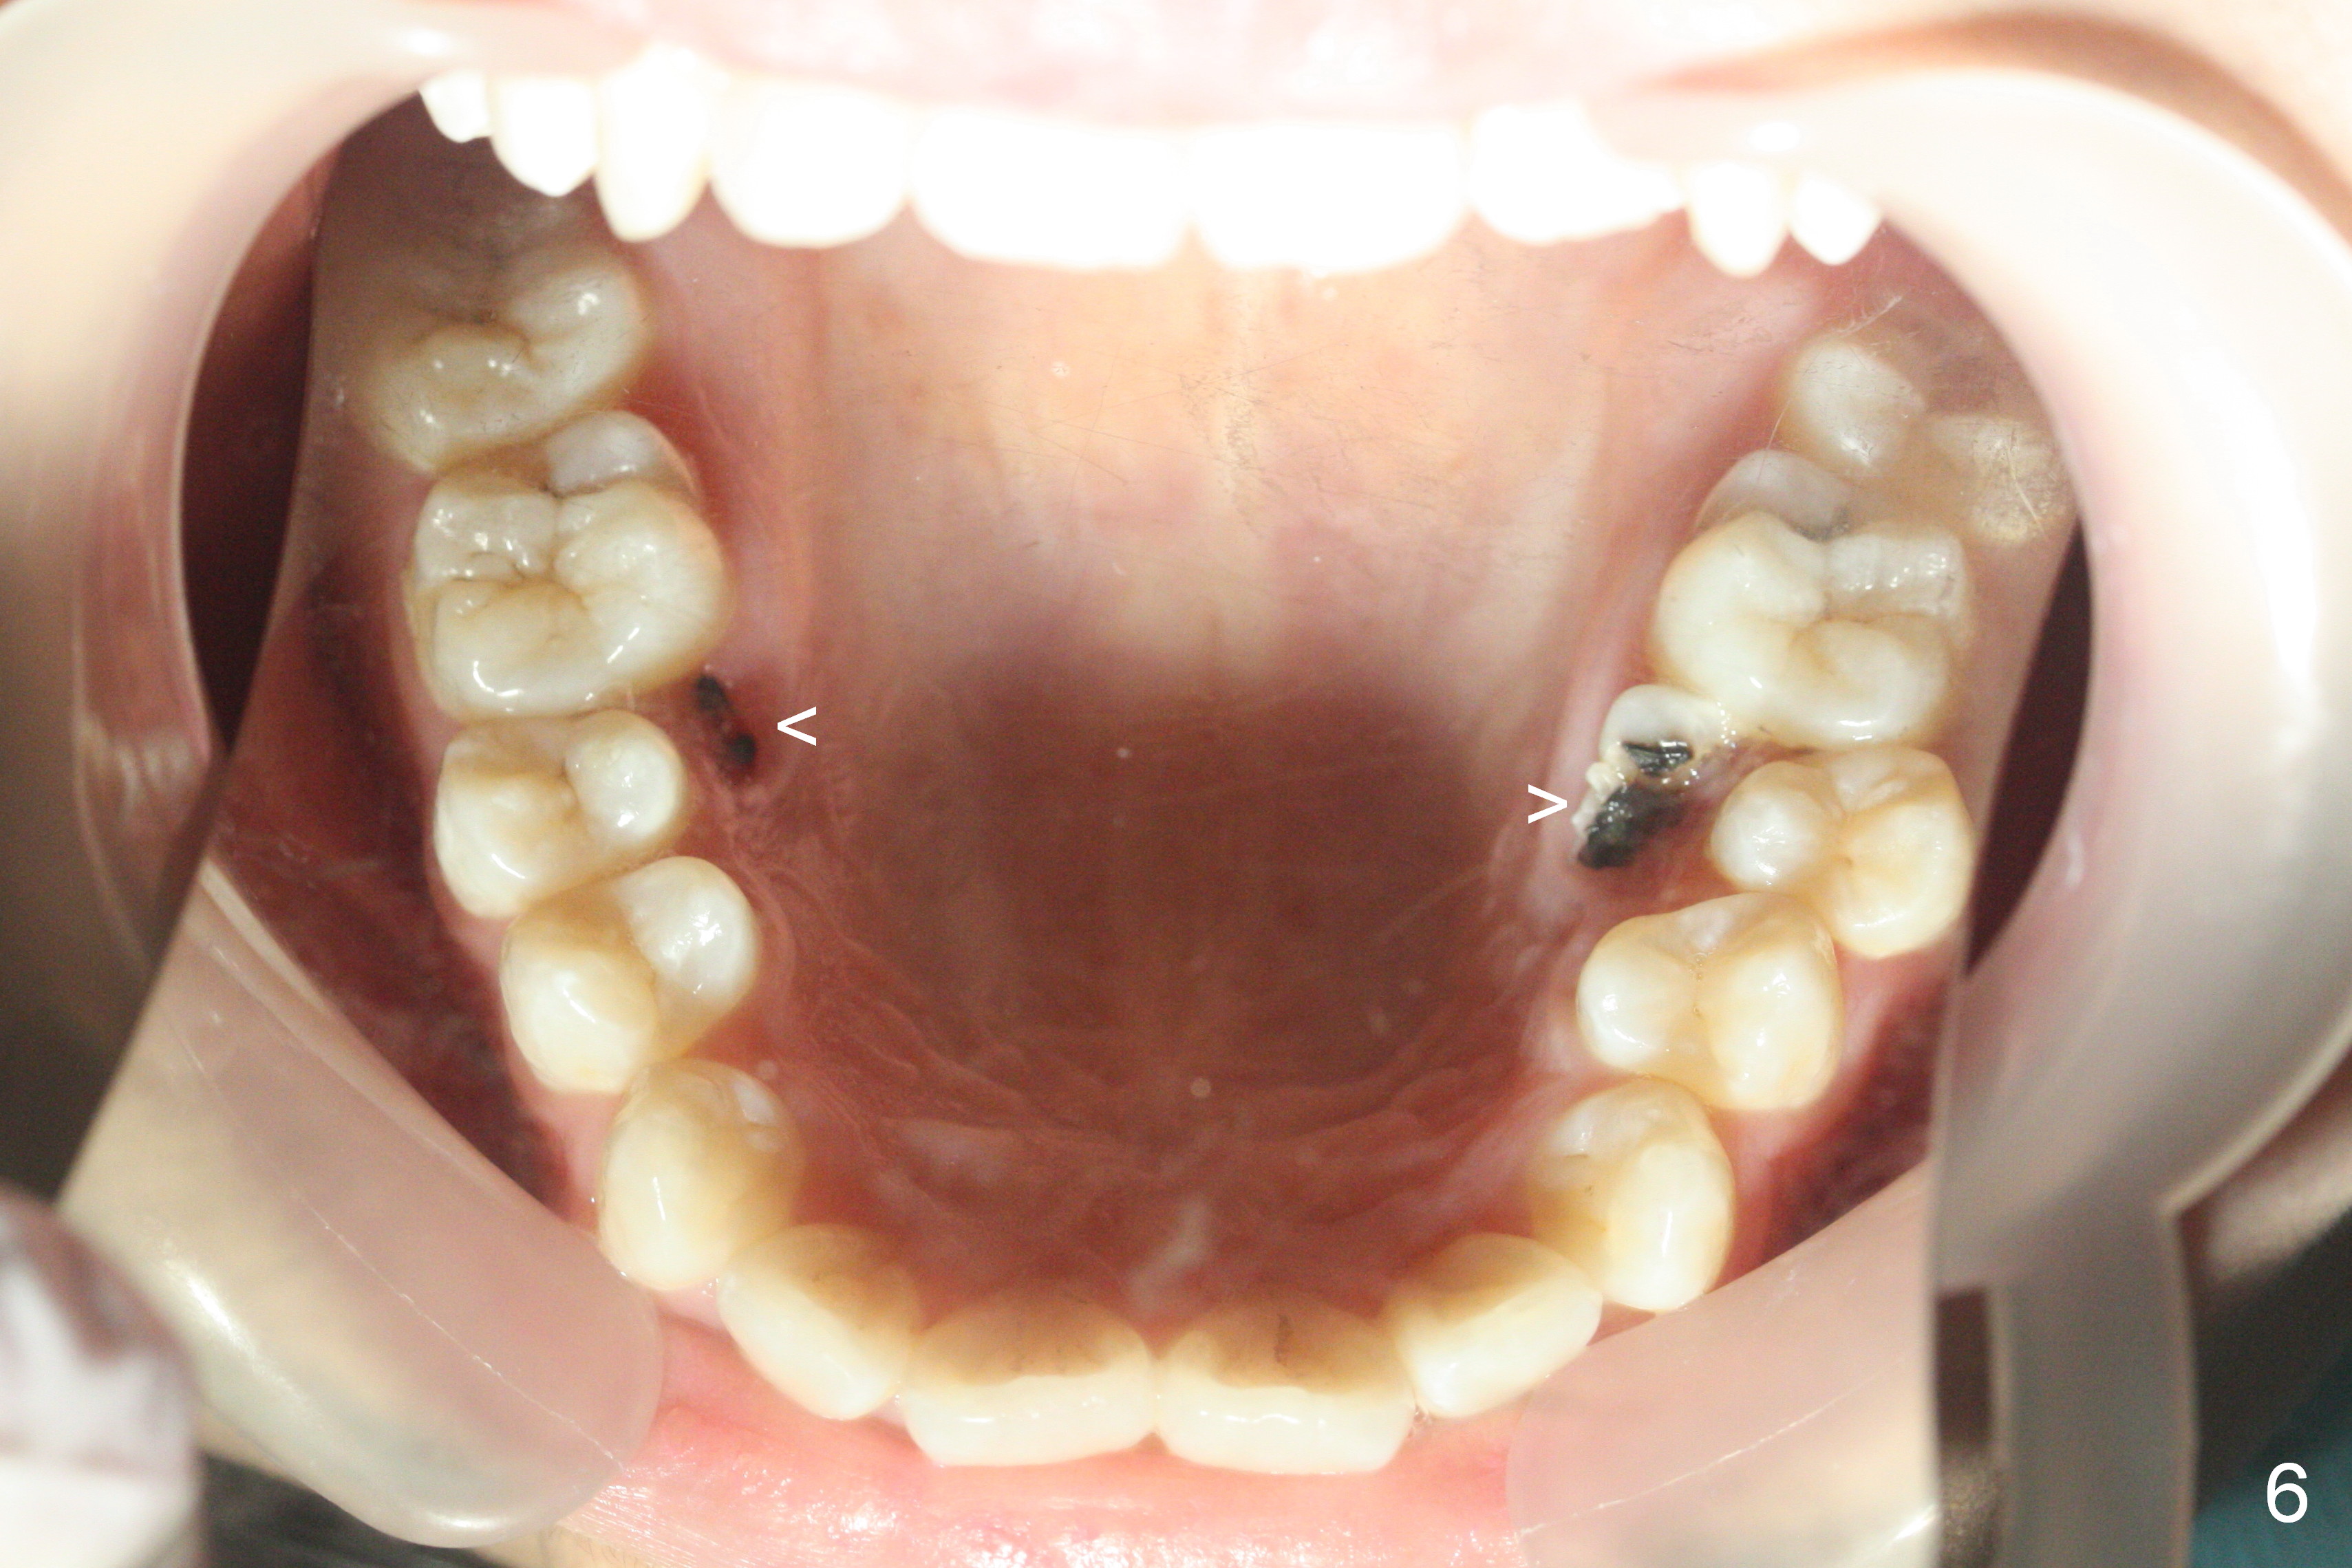

A 17-year-old woman will return for bracketing after caries control and deciduous tooth (Fig.6 arrowheads) extraction. Her profile is slightly protrusive (Fig.1,2). Crowding is more severe in the left posterior region (Fig.4) than the right one (Fig.3). The anterior crowding is also severe (Fig.5). Proximal reduction and use of power chain for constriction will be used instead of extraction of 4 bicuspids. Third molar extraction may have to be done prior to banding, especially for the lower right 2nd molar (Fig.7).

By looking at preop models (Fig.8-13), do you think whether extraction is a better option than non-extraction? Class II occlusion on the right (Fig.8), Class I on the left (Fig.10). With extraction of the 1st bicuspids, the posterior occlusion could be normal with further anterior protrusion (Fig.11). The upper arch is rounded (Fig.12); without extraction, the arch may turn out to be U-shaped. The lower arch is more crowded (Fig.13). Without space, the lower right 2nd molar may not be uprighted (Fig.7).